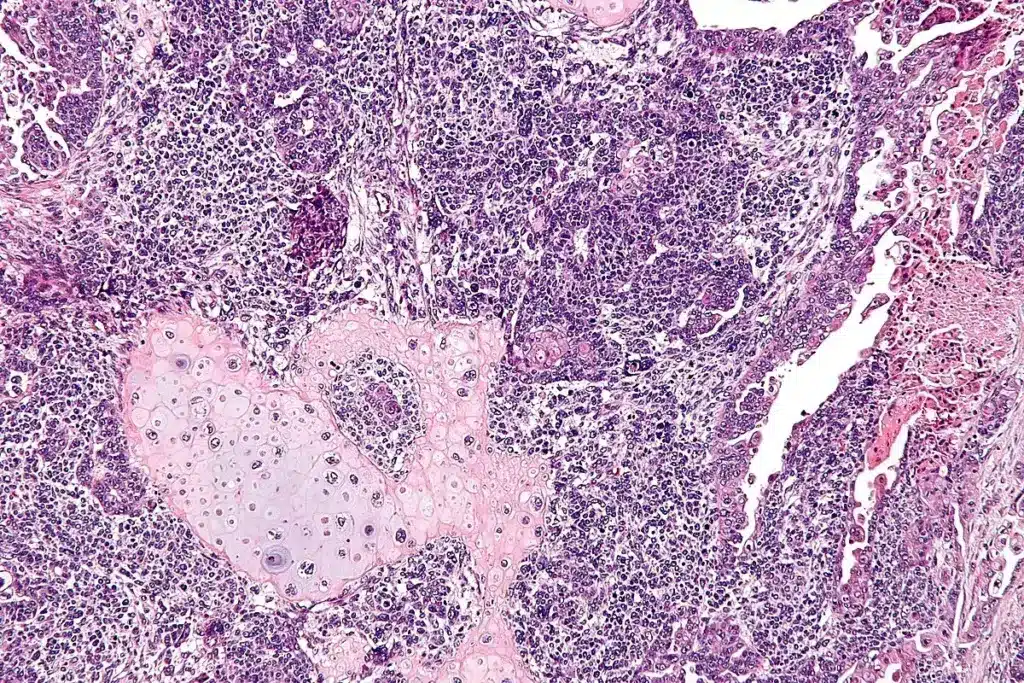

What is adenoid cystic carcinoma?

Adenoid cystic carcinoma (ACC) is a specific subtype known for its “nest-like” appearance under a microscope. It is particularly noted for perineural invasion, meaning it tends to travel along nerve fibers. While often slow-growing, it requires very long-term follow-up because it can recur years after treatment.